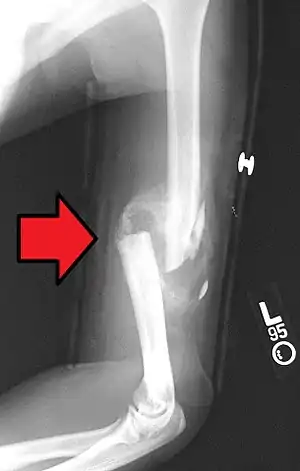

Comminuted midshaft humerus fracture with callus formation.

A fibrocartilage callus is a temporary formation of fibroblasts and chondroblasts which forms at the area of a bone fracture as the bone attempts to heal itself. The cells eventually dissipate and become dormant, lying in the resulting extracellular matrix that is the new bone. The callus is the first sign of union visible on x-rays, usually 3 weeks after the fracture. Callus formation is slower in adults than in children, and in cortical bones than in cancellous bones.[1]